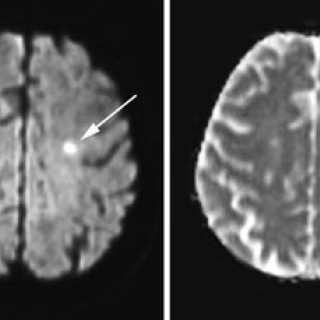

Den første detaljerte beskrivelsen av cerebral venetrombose, også kalt sinusvenetrombose, ble forfattet av Ribes i en artikkel fra 1825 (1). Siden fulgte en rekke kasuistikker basert på autopsimaterialer, som førte til den oppfatning at cerebral venetrombose representerte en sjelden, alvorlig sykdom karakterisert med hodepine, papillødem, epileptiske anfall, fokale utfall, progredierende koma og død (2, 3). Introduksjon av moderne nevroradiologisk utredning har gjort diagnostisering intra vitam mulig, dermed er det blitt klart at sykdomsutviklingen ved cerebral venetrombose heller sjelden er i...